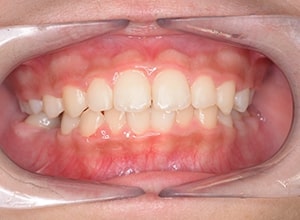

| 口腔内所見 | over jet 3.5mm,over bite4.0mm、下顎正中右側偏位2.0mm、大臼歯関係は左側Ⅰ級であったが、右下6は右下E早期喪失のため近心傾斜しておりⅢ級の臼歯関係となっていた。また上下顎前歯は軽度の叢生を呈していた。 |

| 批評・予后 | 右下5及び7の萌出前に右下6を整直させることによって、右下5の自然萌出が可能となり正常咬合への咬合誘導が行えたと思う。 |